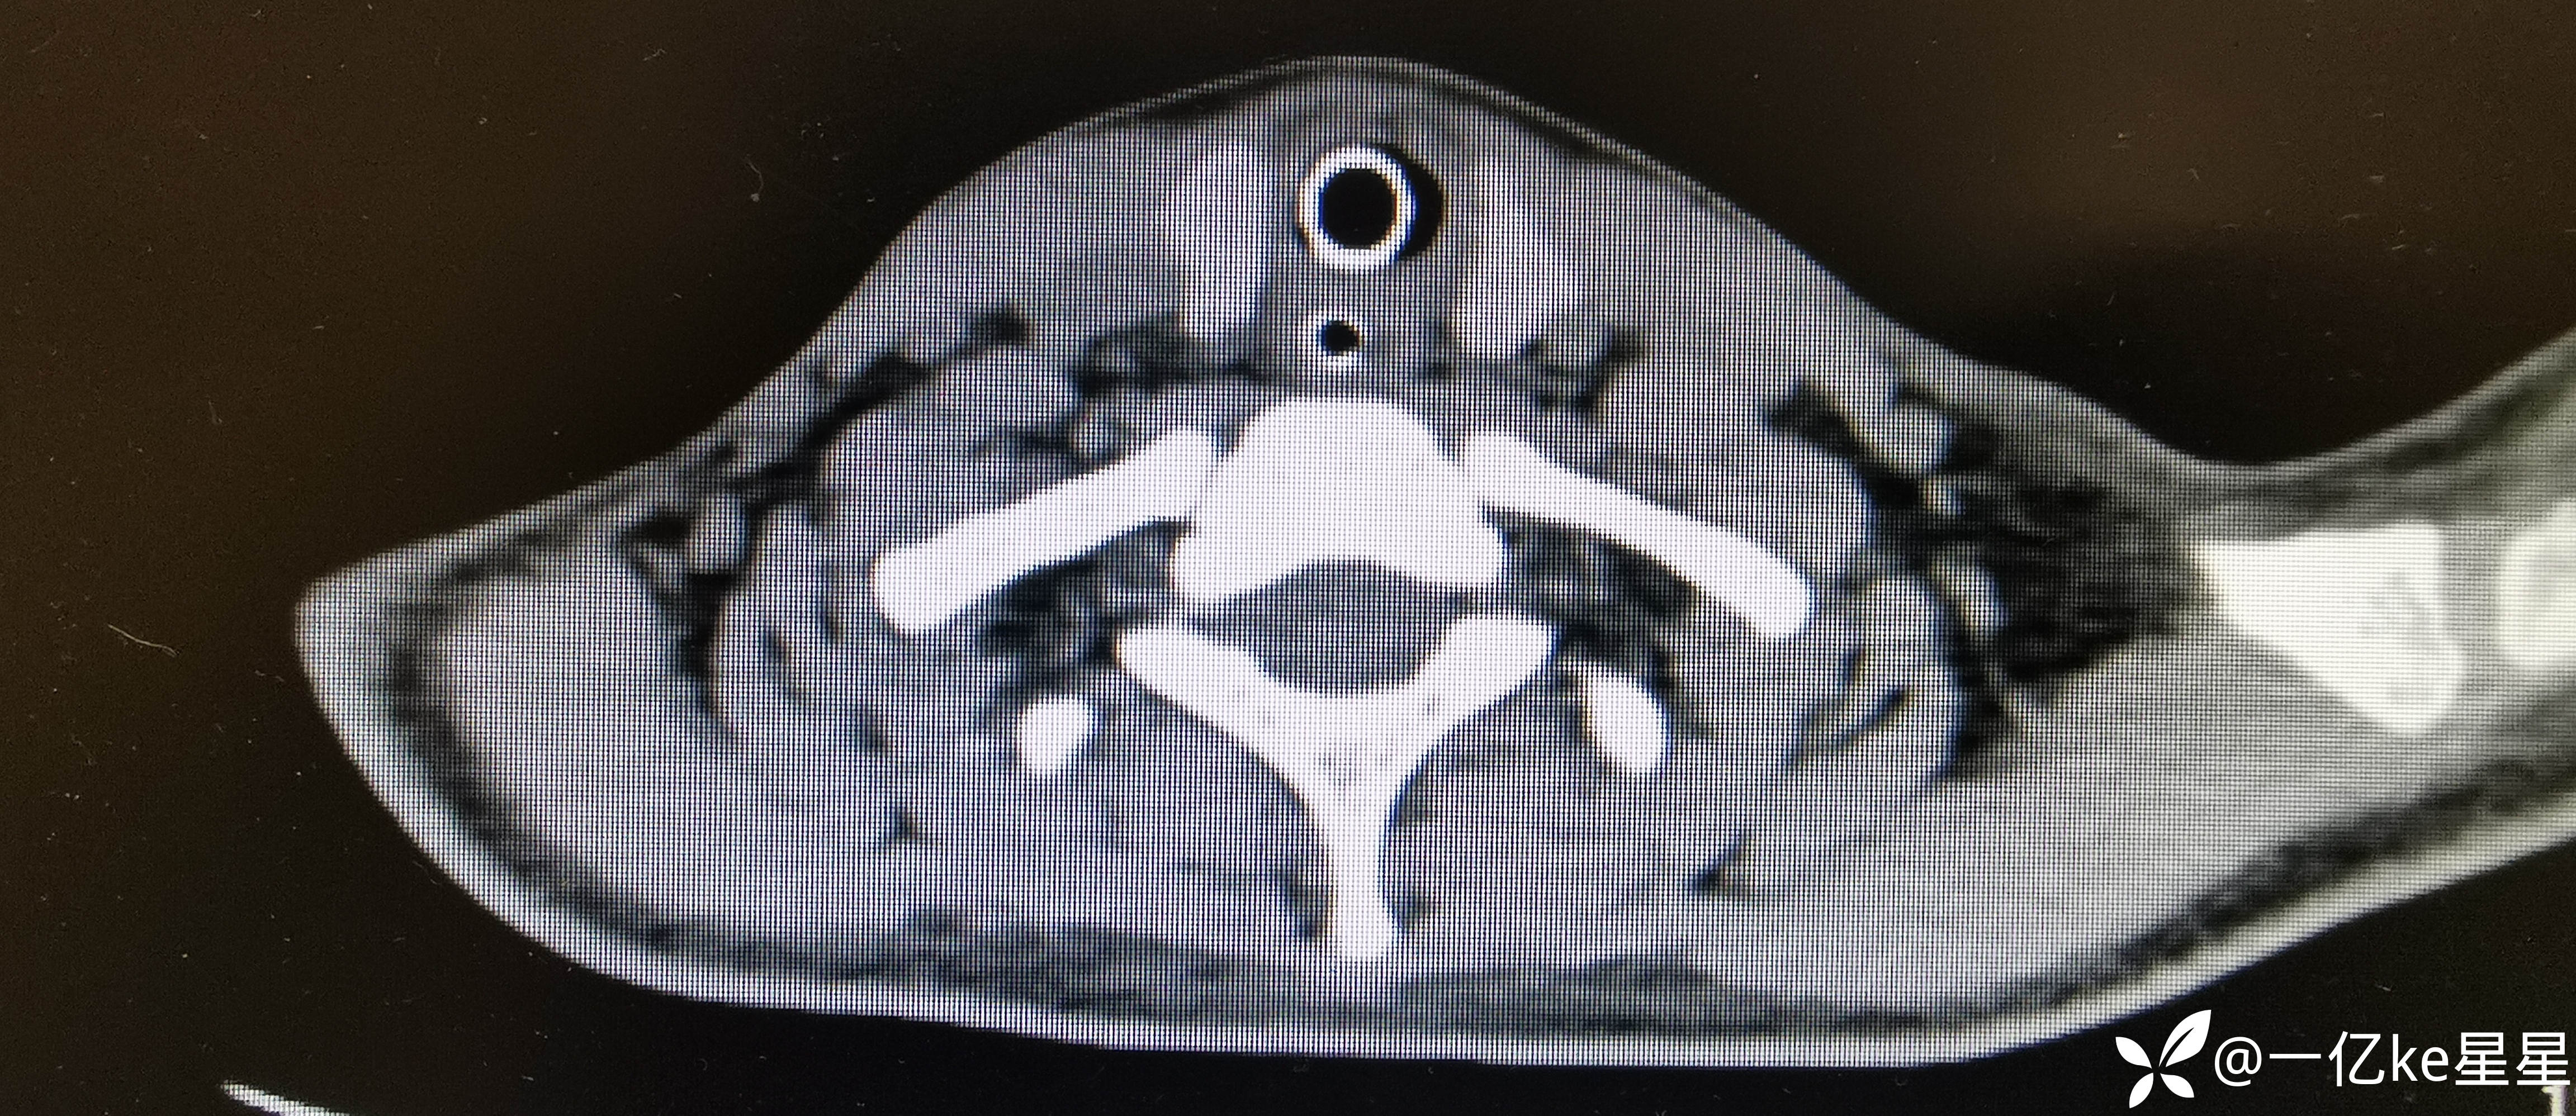

进一步完善支气管镜检查:

考虑患者气管切开时间长,出现气管切开上段气道塌陷,进一步行T管置入术,术后复查胸部CT(2023.12.27)。